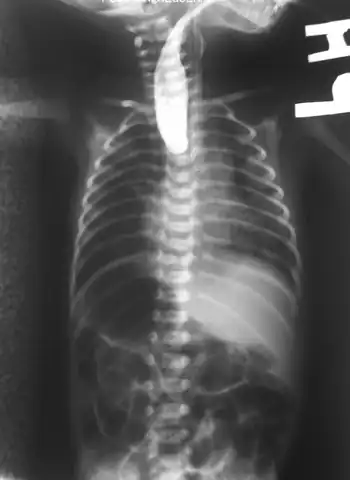

Plain x-ray with contrast in the upper esophagus above the atresia.